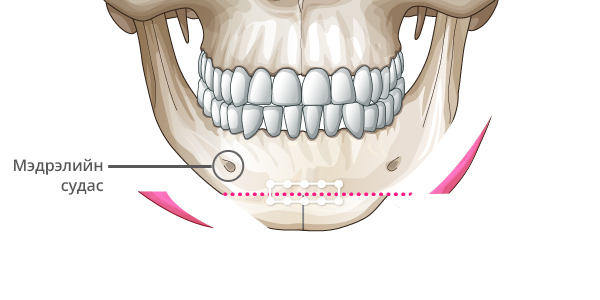

Step 4

Хоёр талд товойж гарч ирсэн ясны хэсгийг тайрч авна.